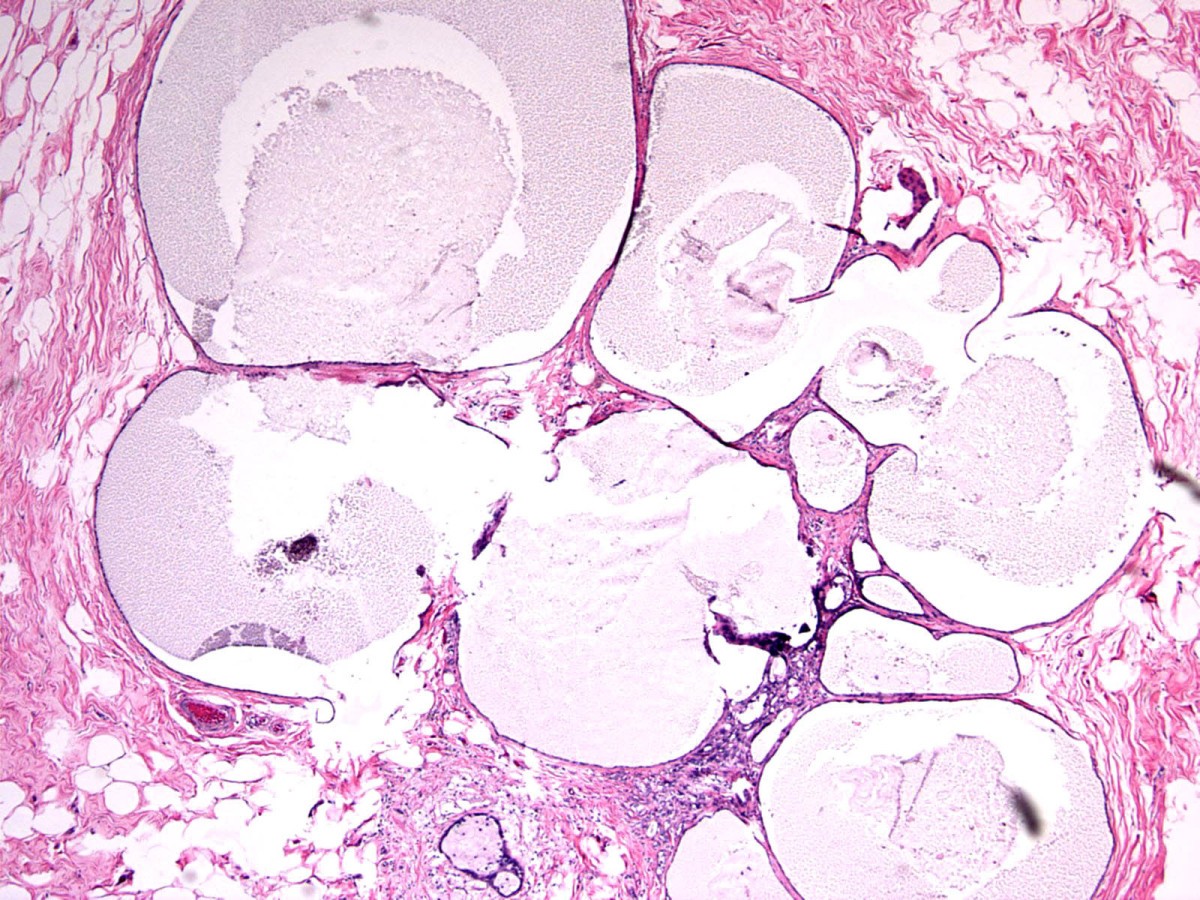

What Is Columnar Cell Hyperplasia . But essentially there are two categories of columnar cell breast lesions; Stratified columnar epithelial cells forming. 15,16 simple columnar cell change is considered nonneoplastic, while columnar. Columnar cell lesions (ccls) of the breast are characterized by the substitution of regular layer of cuboid epithelial by columnar. The image demonstrates the histologic features of columnar cell hyperplasia: Columnar cell lesions are thus a common finding in the setting of mammographic calcifications. Columnar cell change, in which a single layer of.